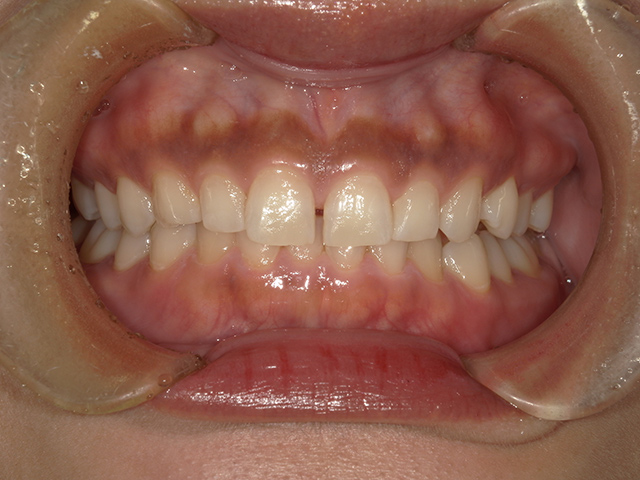

ダイレクトボンディングとは、高品質なレジン(樹脂)を直接歯に盛り付け、形や色を1本1本丁寧にデザインする審美修復治療です。

天然歯のような透明感や質感を再現できるため、近年非常に人気が高まっています。

自然で美しい仕上がり

使用するレジンは、色調・明度・透明感を細かく調整できる審美レジン。

歯科医師が職人のように層を重ねながら形を作り、天然歯と見分けがつかない仕上がりを目指します。

すきっ歯・欠けた歯の修復に最適